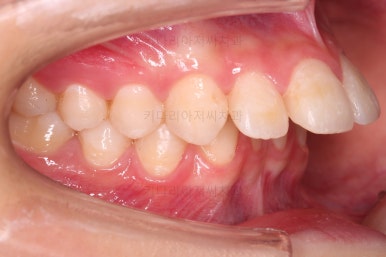

초진 시 입안의 모습입니다.

어금니 맞물림은 지그재그로 잘 맞물려 있는데 위아래 앞니는 서로 앞뒤로 매우 멀죠.

비밀은 매우 자연스러워 보이지만 아래 앞니 2개가 선천 결손인 상태였습니다.

앞니끼리 맞물리지 않다보니 아래 앞니는 점점 솟구쳐 과개교합(깊게 맞물려 아래 앞니가 거의 보이지 않는 현상)이 되게 됩니다.

치아 갯수를 맞추고 튀어나온 앞니를 넣기 위해서 윗니 중간의 작은 어금니를 발치를 했고요.

아래는 통째로 앞으로 끌고 나오기로 했습니다.

아래턱은 아쉽게도 성장 시킬 수 있는 나이는 지났고, 대신 가능한 선에서 아랫니를 앞으로 빼보기로 했습니다.